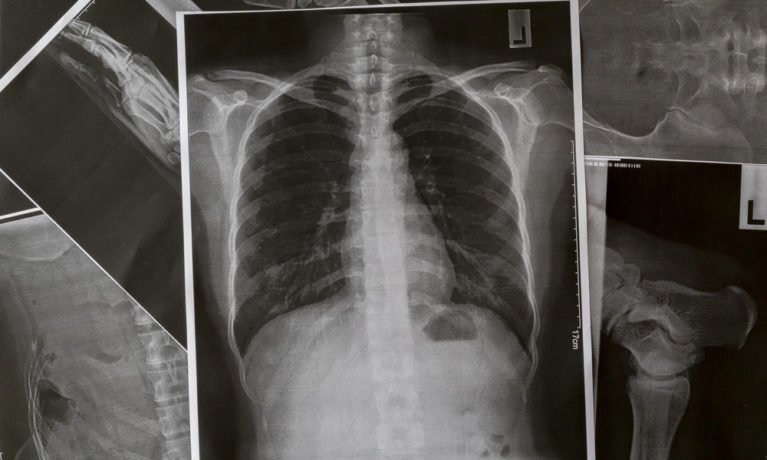

Theo tiêu chí của Reader, thuyên tắc phổi là một căn bệnh nghiêm trọng xảy ra khi cục máu đông chặn các mạch máu trong phổi. Các cục máu đông thường phát triển trong một bộ phận của cơ thể (thường là chân) và sau đó chảy đến phổi. -Nhiều người bị thuyên tắc phổi, nhưng hoàn toàn không biết về nó. Trong tình huống nguy hiểm, các triệu chứng đầu tiên của bệnh cũng là triệu chứng nghiêm trọng dẫn đến tử vong.

Ở một số bệnh nhân, dấu hiệu đầu tiên của thuyên tắc phổi là sau khi một cục máu đông đi vào phổi. Triệu chứng phổ biến nhất là khó thở. Bệnh thường tiến triển đến trạng thái nguy kịch khá nhanh. Bệnh nhân có thể cảm thấy khỏe vào ban đêm, nhưng khó thở vào sáng hôm sau.